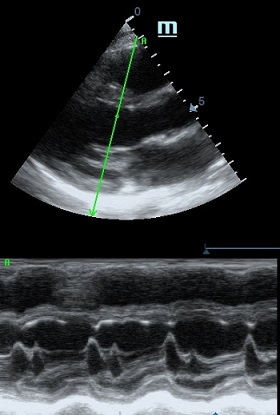

MAPSE - амплитуда движения латерального кольца митрального клапана, позволяет рассчитать фракцию выброса по формуле EF = 4.8 × MAPSE (mm) + 5.8, очень быстрый и гораздо более точный («прародитель Strain») метод чем широко распространенный метод Teicholtz. В современных приборах можно легко добавить свою формулу при отсутствии ее в стандартном калькуляторе. Главным условием является проведение линии М-режима параллельно стенке левого желудочка в апикальном четырехкамерном сечении, что легко достигается при использовании функции Free Xros.